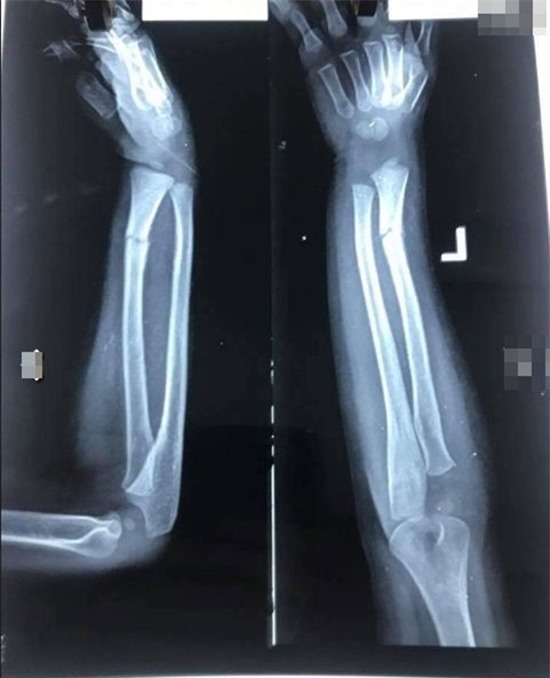

Qua

những hình ảnh có thể thấy được tay trái của bé trai bị gãy phải bó

bột, cùng nhiều vết lằn đỏ. Bên cạnh đó tài khoản facebook này còn cung